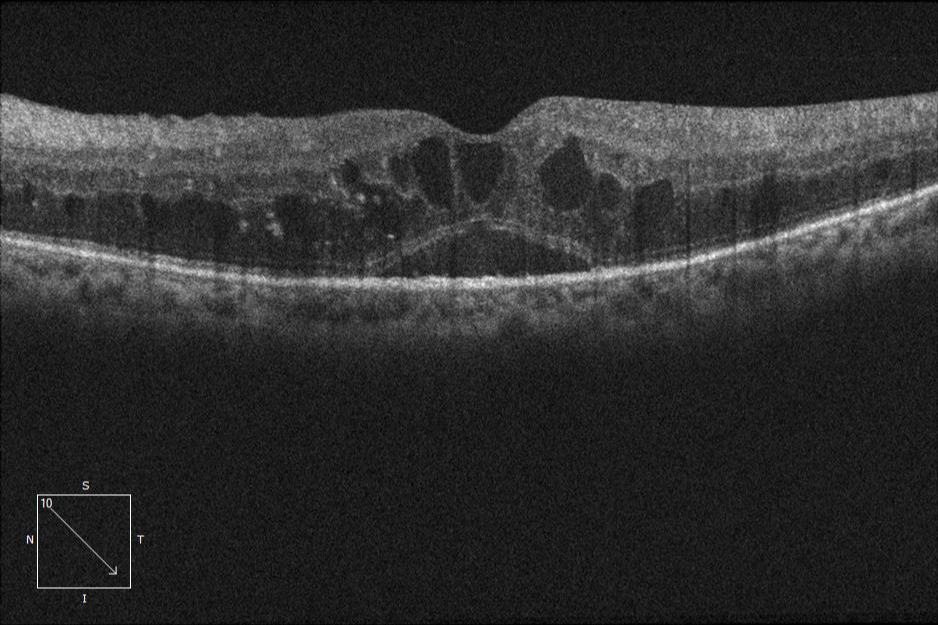

- Edema macular diabético (EMD) con disminución visual.